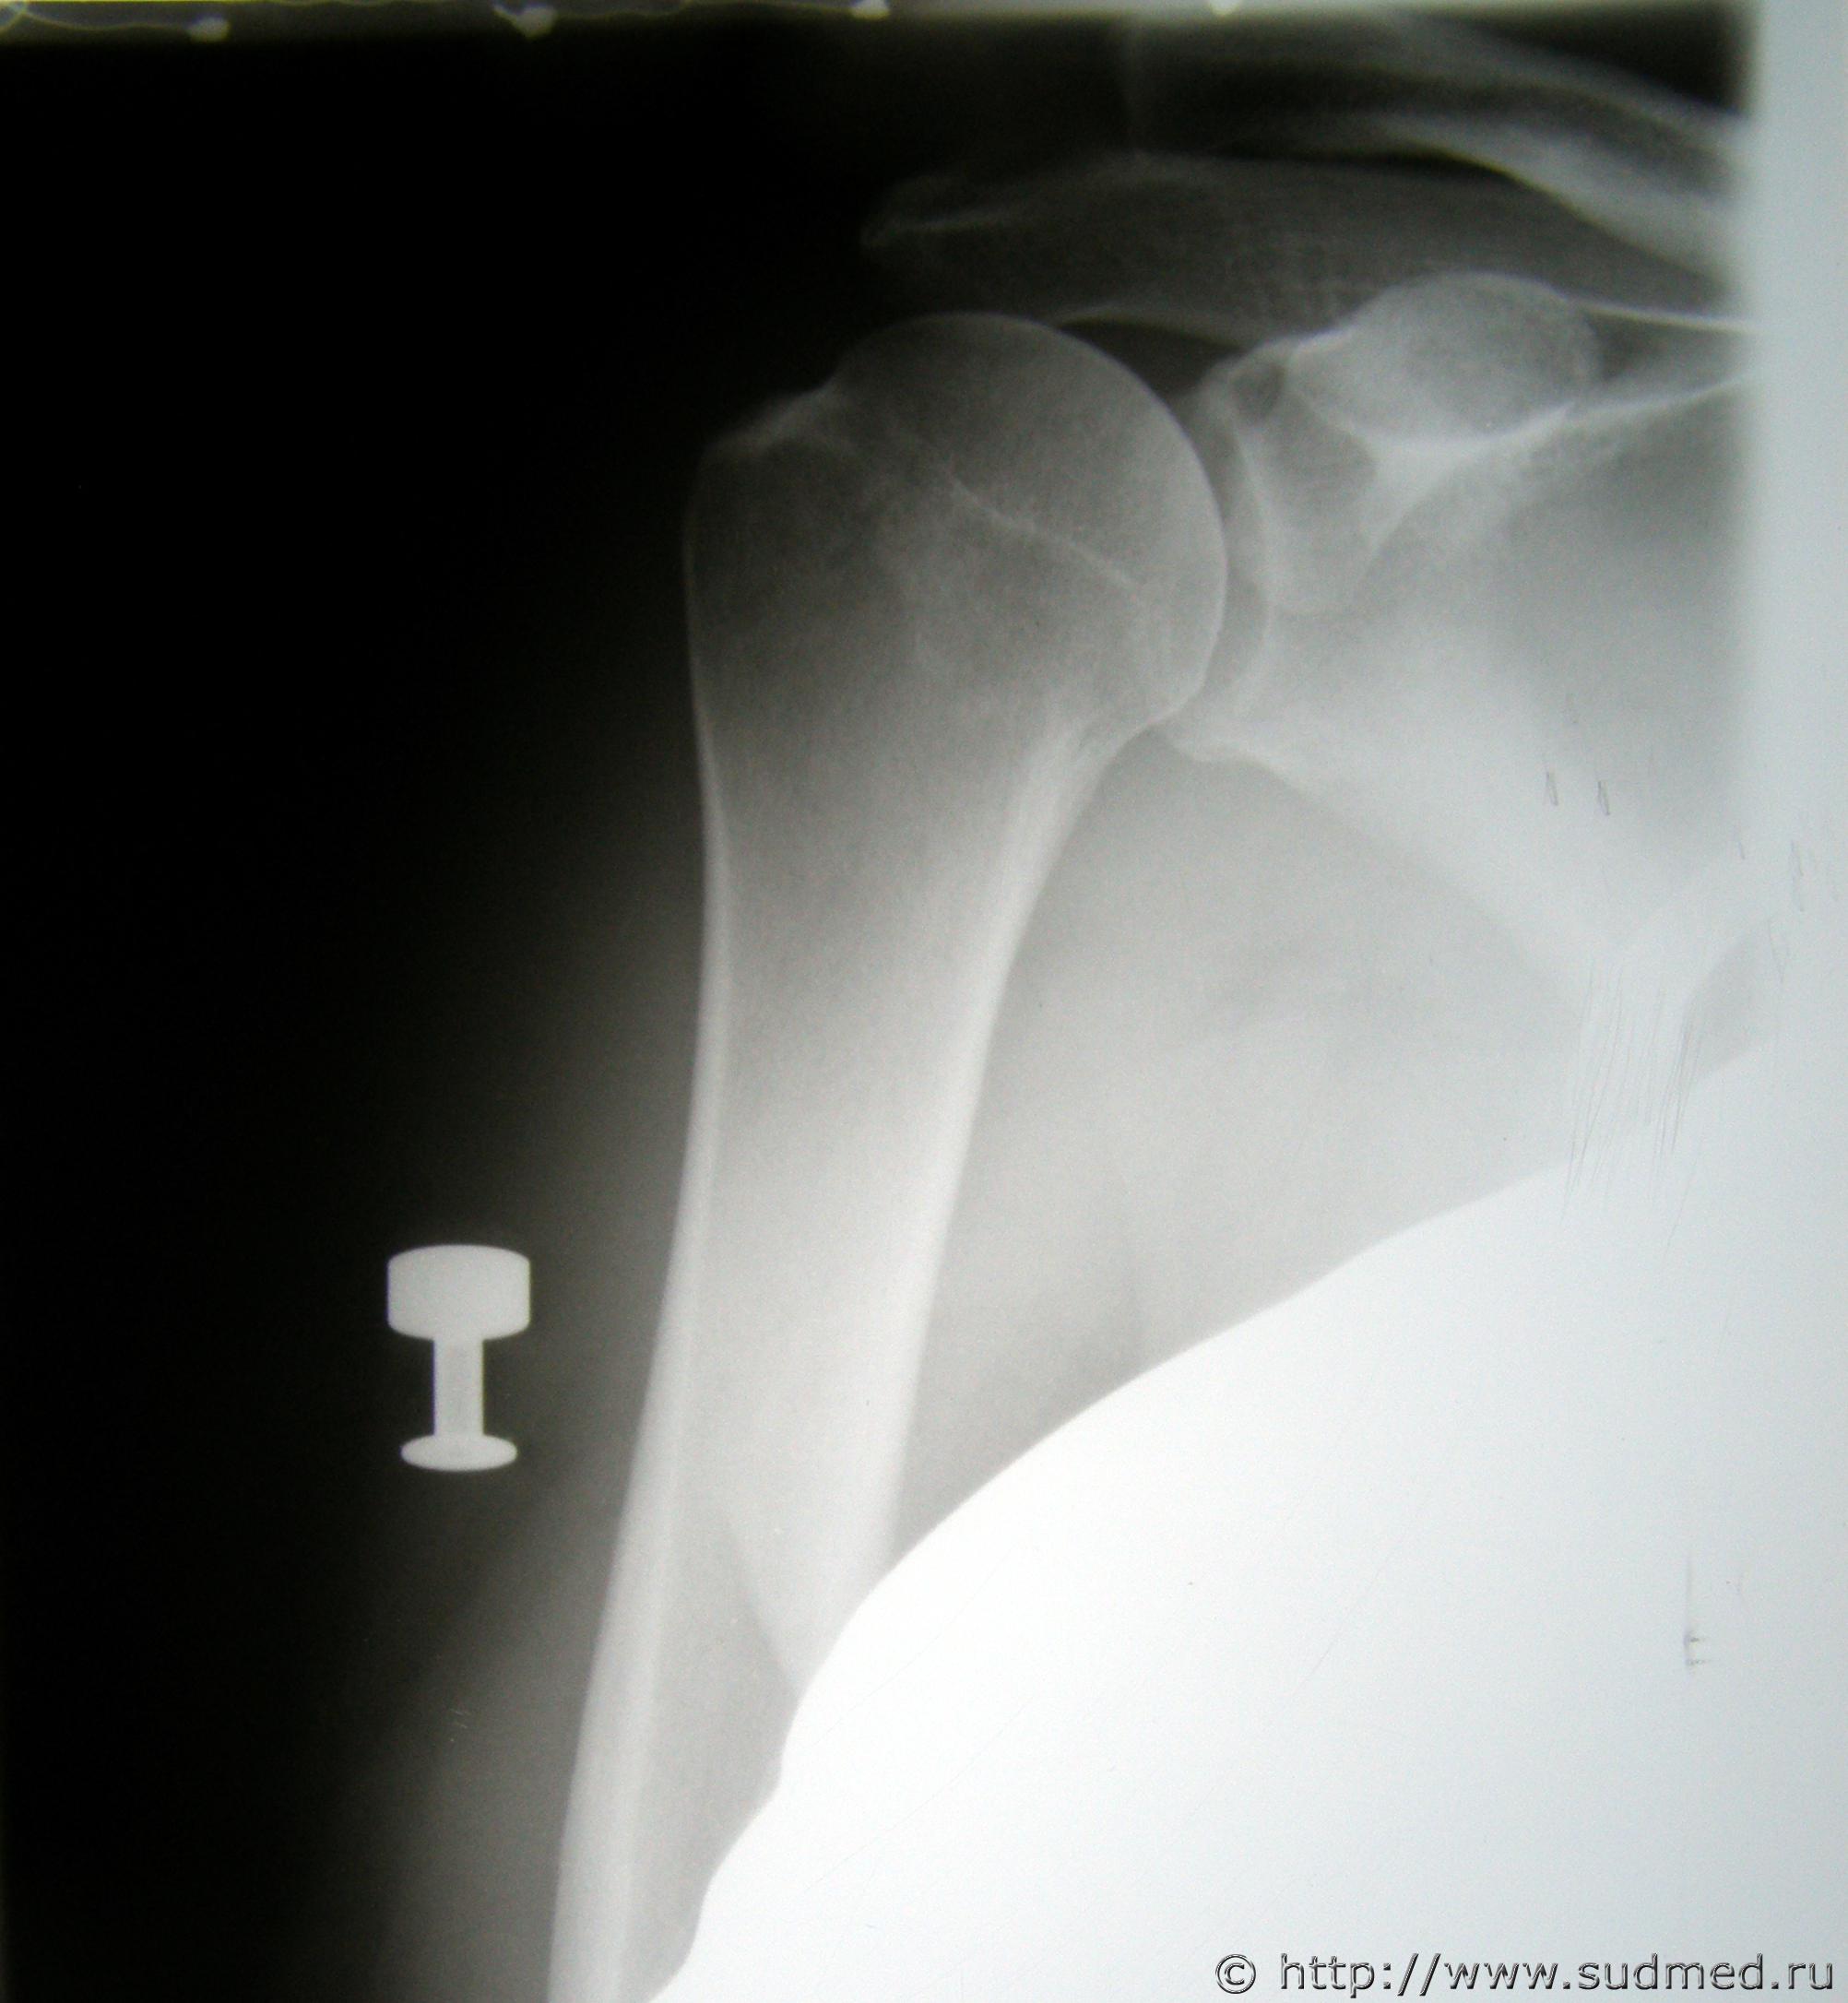

На рентгенограмме металлический сердечник резиновой пули от пистолета "Оса" в мягких тканях правого плеча.